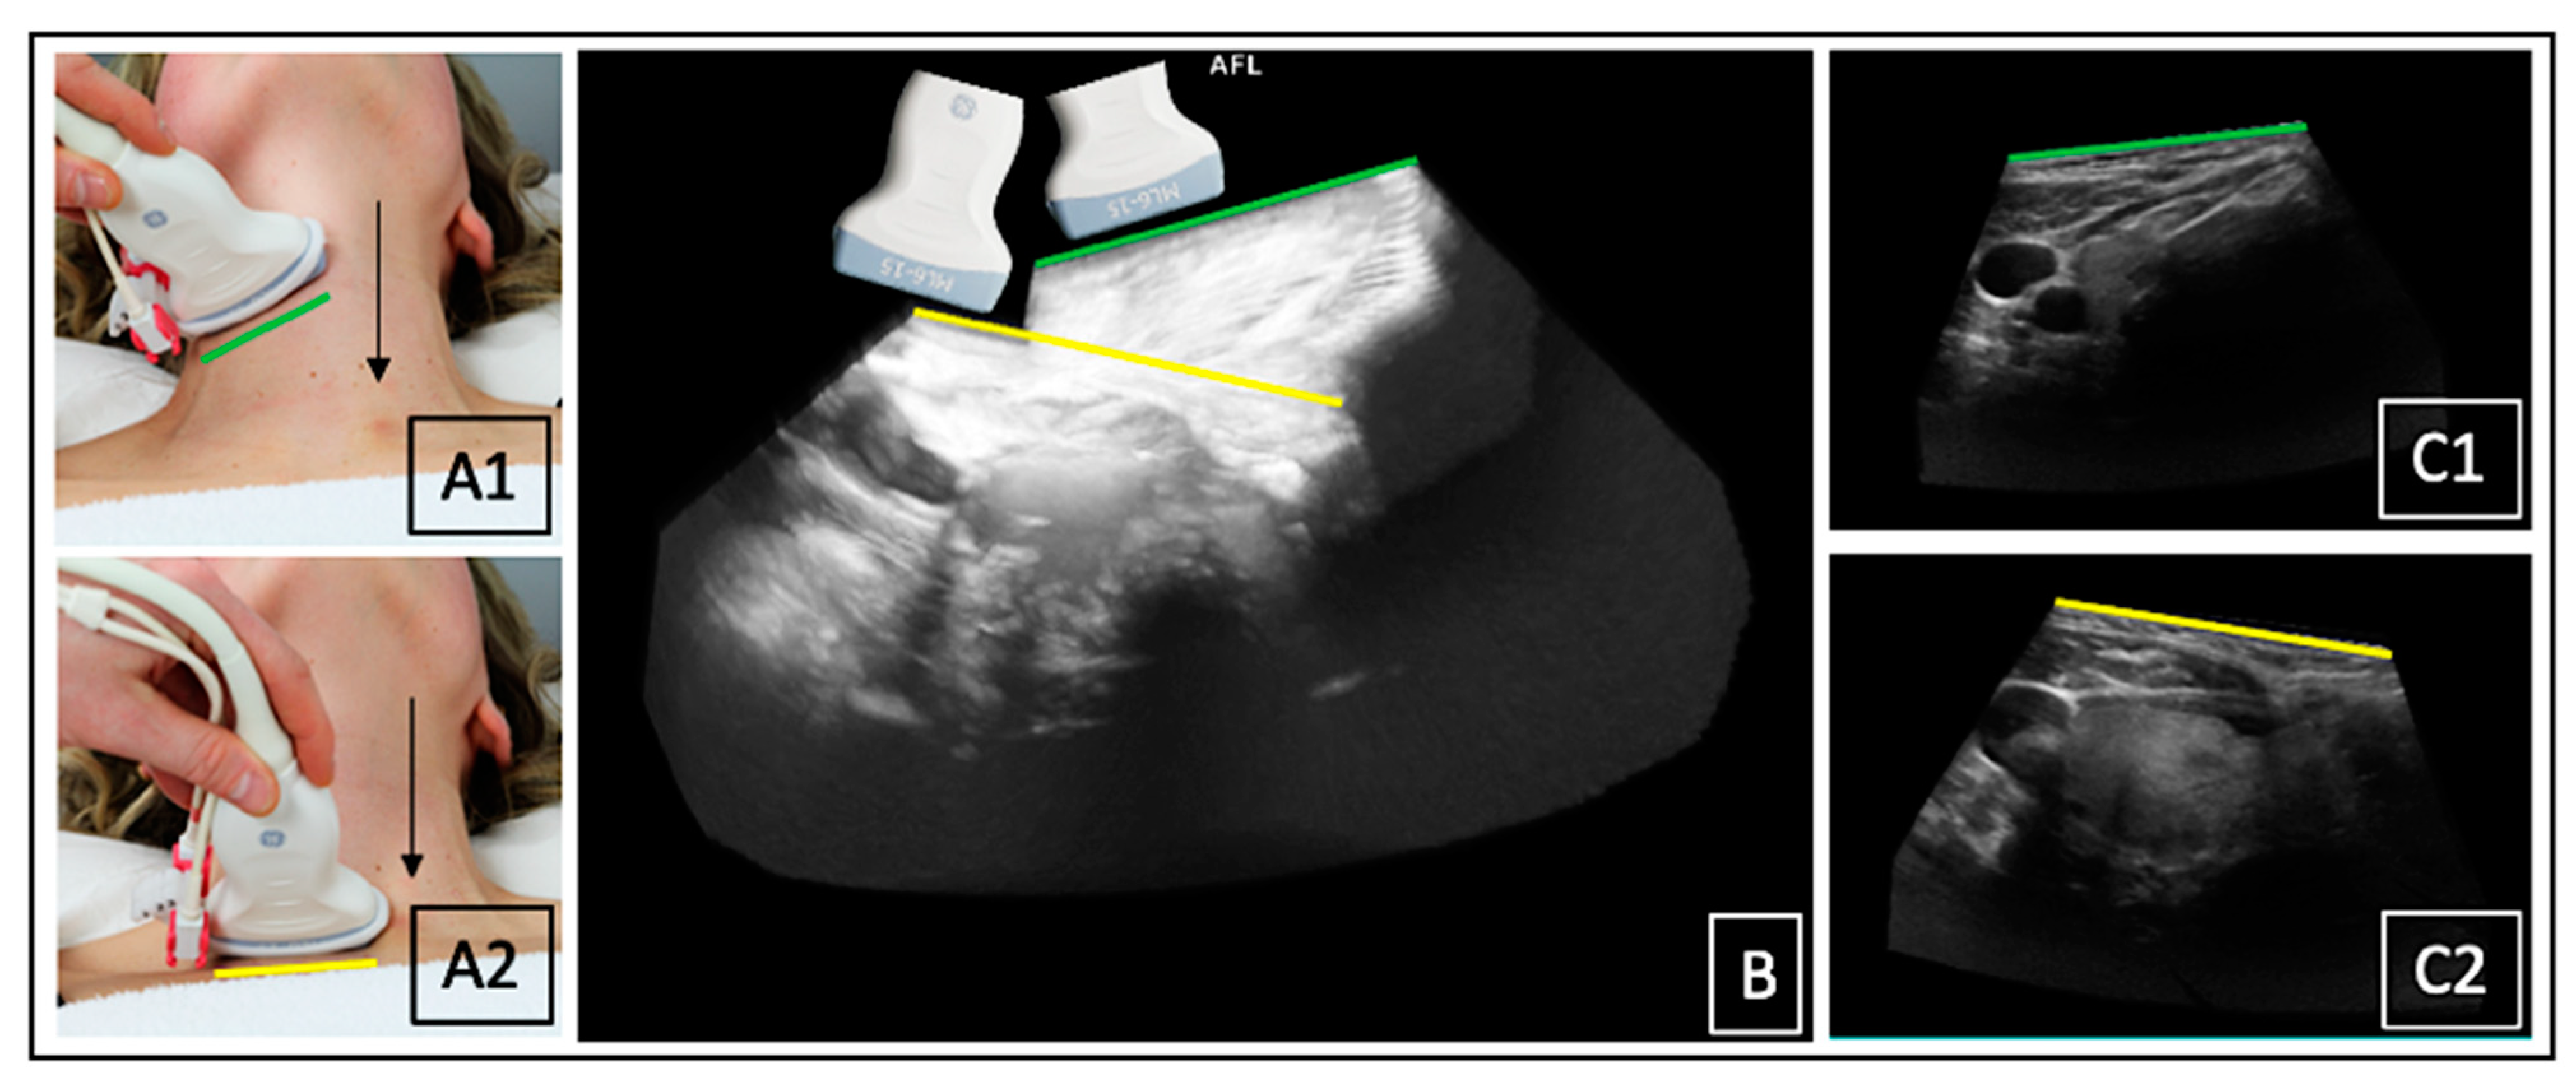

US was performed on the LOGIQ E9 device (GE Medical Systems, Milwaukee, WI, USA). Separate scans of each thyroid lobe (left and right) were acquired. ConUS was conducted with the linear matrix array ML6-15 according to a local standard operating procedure [7]. For 3DsnUS, a magnetic field and specific position sensors equipped to the ML6-15 probe were necessary. For 3DmsUS an automated mechanically swept 3D convex probe (RAB4-8) was used. The methodology of these 3D-US applications has been described in several previous publications [14,19,20]. All 3D-US data sets were transferred to the research software PMOD (Version 4.1, PMOD Technologies Ltd., Zürich, Switzerland). Examination settings and acquired data sets are depictured in Figure 1 and Figure 2.

Figure 2.

3DmsUS: constant fixation of the probe orthograde to the neck surface ((A), right angle); movement of the automated mechanically swept acoustic element inside the probe ((A), black arrow), acquired image sector ((A), red box), and reconstructed 3DmsUS data set on the US device (B). (C) shows a 3DsnUS data set of a right thyroid lobe displayed in the PMOD software in three dimensions: transverse ((C), a, red box), sagittal ((C), b, white box), coronal ((C), c yellow box).